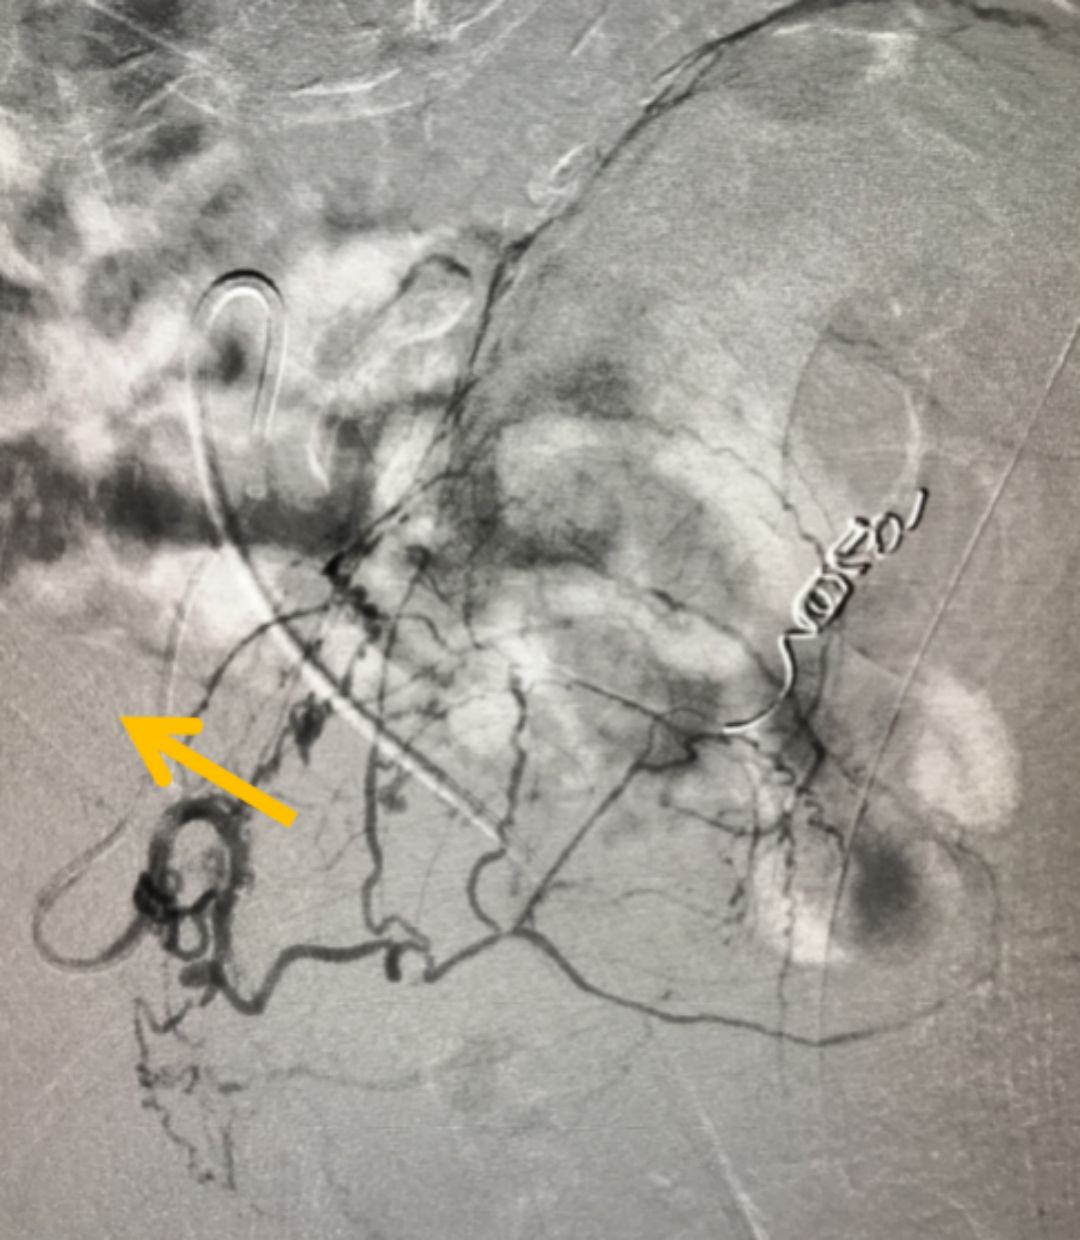

图:增生的前列腺(箭头所指)挤压尿道,导致排尿困难

在全面评估后,团队为他制定了PAE的精准治疗方案。手术仅通过大腿根部一个针眼大小的穿刺点,将比头发丝还细的微导管,在影像引导下精准送入供养前列腺的动脉,并注入安全的栓塞微粒。这个过程,就像精准地“断粮”

图:微导管(箭头所指)